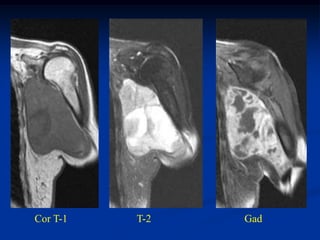

Case #258.4      Axial T-1            T-2

Gad

65 yr old male with painful

mass in buttock for 4 months

Cor T-1   T-2

Sag T-2   Gad

Case #258.4 Axial T-1 T-2 Gad 65 yr old male with painful mass in buttock for 4 months

• 131.

Cor T-1 T-2 Gad